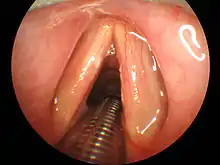

Classically, tracheal intubation has been performed utilizing direct laryngoscopy to obtain direct visualization of the vocal cords. There are multiple different laryngoscope blade styles, shapes, and lengths from which to choose based on patient anatomy and clinician preference.[9] In North America, the Macintosh blade is the most commonly used curved blade while the Miller blade is the most common straight blade.[9] Many modern laryngoscopes are equipped with a fiberoptic light source to aid in visualization. Regardless of blade shape, direct laryngoscopy technique involves passage of the laryngoscope through the mouth and into the back of the throat. Manipulation of the neck and lifting of the tongue allows for direct visualization of the larynx and vocal cords by the operator. Following visualization, the endotracheal tube can be passed along the blade, through the vocal cords, and into the trachea.[10]

Multiple intubation tools are now available with built-in video technology, also known as video laryngoscopy.[9] The GlideScope model utilizes a curved laryngoscopic blade with an integrated camera connected to a large external monitor. The McGrath model has a compact design with a small display directly attached to the laryngoscopic blade. The operator introduces the video laryngoscope through the mouth with a technique similar to direct laryngoscopy. The larynx and vocal cords are visualized via the camera and the operator is able to pass the endotracheal tube through the vocal cords and into the trachea under direct visualization on the video monitor.[9] Studies have shown that when compared to direct laryngoscopy, video laryngoscopy resulted in fewer failed intubation attempts, especially in patients with known difficult airways.[11] Limitations of video laryngoscopy exist and prevent the exclusive use of this method over direct laryngoscopy. Excessive blood and saliva in the airway can cover the camera lens on the video laryngoscope and obscure effective visualization of the anatomy, preventing effective intubation attempts. This is of importance in patients with trauma to their airway, increasing the amount of blood present, and patients taking sialogogues, or drugs that increase the flow of saliva.[12]

In patients with known difficult airways, fiberoptic intubation can be considered. This technique involves the use of a flexible fiberoptic bronchoscope for visualization of the vocal cords. The bronchoscope can be passed directly into the trachea and the endotracheal tube can be threaded over the bronchoscope into position. This technique has various advantages over direct laryngoscopy and video laryngoscopy techniques. The fiberoptic scope is flexible and can be directed by the operator, allowing it to traverse the upper airway with minimal manipulation of the patient's neck. The operator can manipulate the device around obstructions in the upper airway, making the technique advantageous for patients with cancer or swelling in the upper airway. The device is relatively small compared to a laryngoscope and can therefore be implemented in patients with small mouth openings. Additionally, the fiberoptic scope can be passed through the nostril to provide visualization for a nasotracheal intubation. Lastly, fiberoptic intubation can be conducted in an awake patient with sufficient use of local anesthetics, which can prove useful in patients who would otherwise be unable to be anesthetized without having a secure airway in place beforehand. [9]